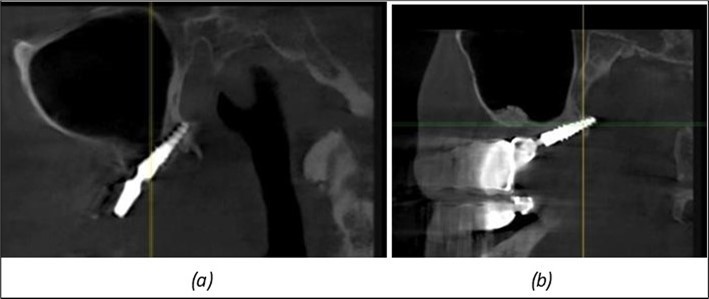

Figure 12.Implants fixed distally in quadrant 4 with fixation at the level of the mylohyoid line: (a) The most distal implant fixed in unaffected bone from the previous restoration; (b) The implant fixed in the area where the two stage implant was removed.

Implants fixed distally in quadrant 4 with fixation at the level of the mylohyoid line: (a) The most distal implant fixed in unaffected bone from the previous restoration; (b) The implant fixed in the area where the two stage implant was removed.